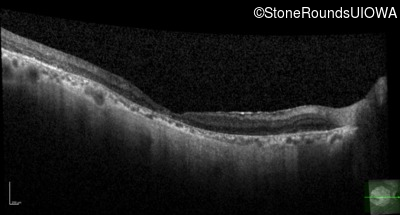

OCT Stack